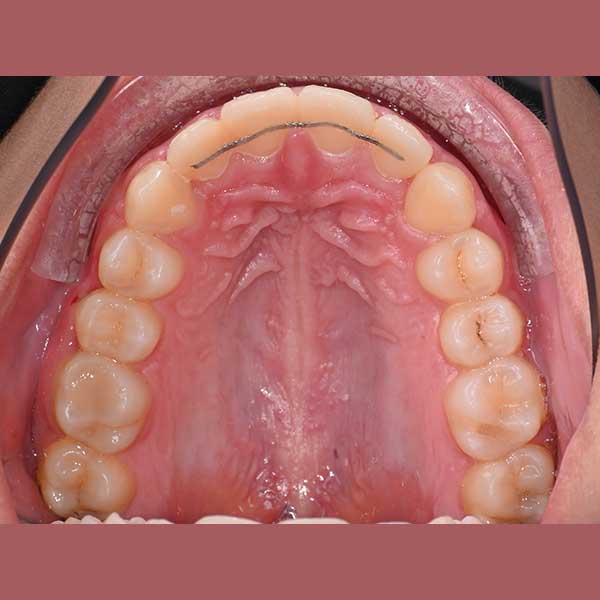

BEFORE

This young woman was suffering from overlapping of her teeth and a lack of sufficient distance of her upper left canine to settle in its natural place, which led to it remaining prominent and higher than the rest of the upper teeth, in addition to the overlapping of her lower teeth greatly, which leads to her inability to clean her teeth well and sedimentation Tartar layers quickly and continuously on these teeth from the back.

By examining the case, it became clear to me that the treatment can be carried out without tooth extraction, through the daemon orthodontic (self-straightening tie), which facilitates the process of expanding the jaws and solving the problem of overlapping.